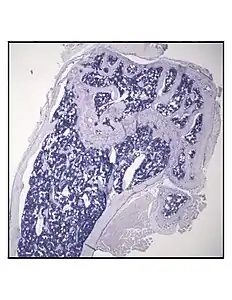

Representative distal femur histologic section of a 16-week-old healthy C57BL/6 mouse demonstrating a typical quantity of marrow adipocytes.

Representative distal femur histologic section of a 16-week-old C57BL/6 mouse after 6 weeks of calorie restriction demonstrating an increased quantity of marrow adipocytes.